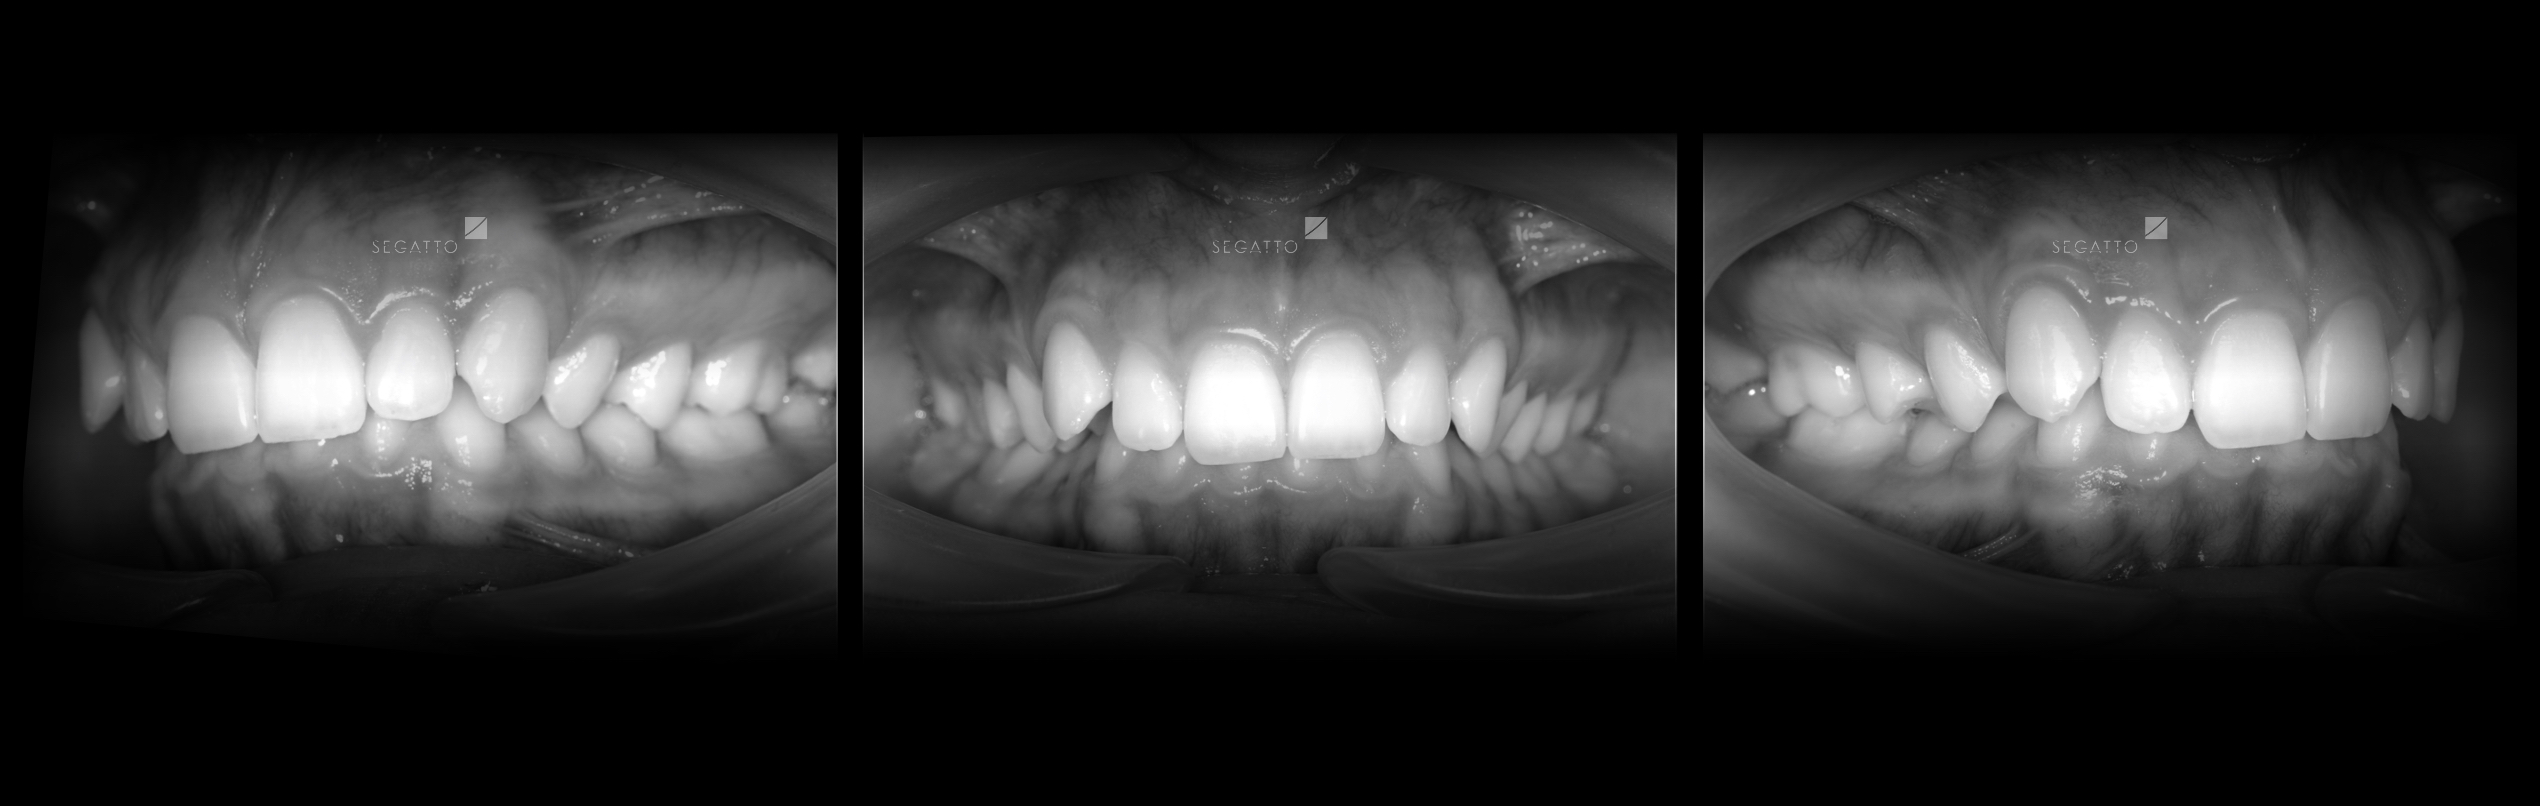

Orthodontics

Cases